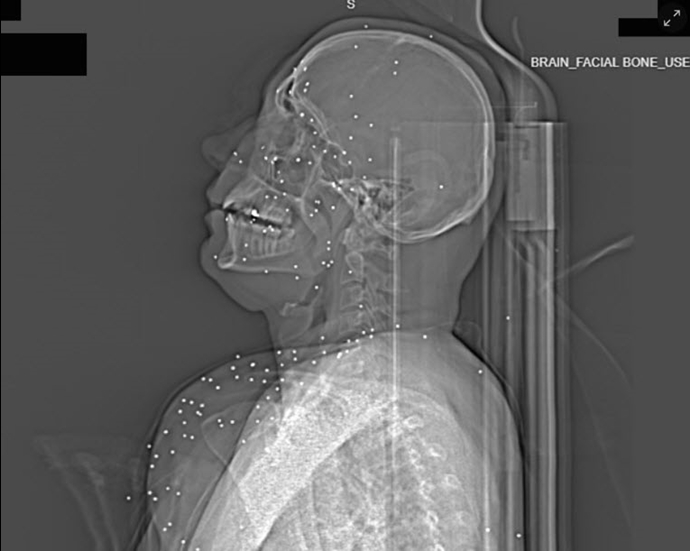

در یکی از این موارد، تصاویر مربوط به زنی جوان با نام مستعار «آناهیتا»* نشان میدهد دهها ساچمه فلزی به اندازه ۲ تا ۵ میلیمتر در صورت، حدقه چشم و حتی بافت مغزی او نفوذ کردهاند. کارشناسان میگویند این ساچمهها که از تفنگهای ساچمهزنی موسوم به «birdshot» شلیک شدهاند، در فاصله نزدیک قادر به خرد کردن استخوان و نابودی کامل بافت نرم هستند. بر اساس گزارش، آناهیتا دستکم بینایی یک چشم و احتمالاً هر دو چشم خود را از دست داده است.

گاردین مینویسد ایران از معدود کشورهایی است که نیروهای مسلح و پلیس آن از ساچمههای فلزی پرندهزنی استفاده میکنند. تصاویر ایکسری نشان میدهد حتی یک یا دو ساچمه نیز میتواند موجب نابینایی یا آسیب دائمی شود. در شلیک از فاصله نزدیک، صدها ساچمه به بدن نفوذ کرده و تمام بافت نرم را نابود میکند.